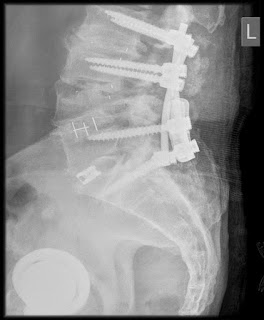

SO, in November 2020, my 3rd back surgery as I basically couldn’t walk anymore

Then another surgery in December 2020–the 4th on my spine!

.…and A FRACTURED SPINE!